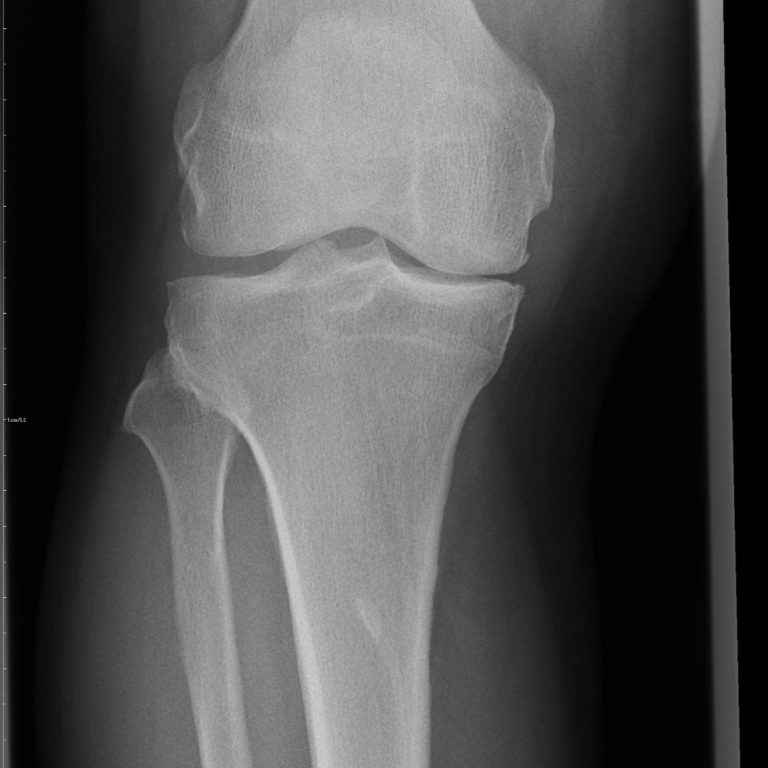

Degenerative Erkrankungen

Verschleißbedingte Erkrankungen:

Arthrose der großen und kleinen Gelenke, Osteoporose, Blockierungen.